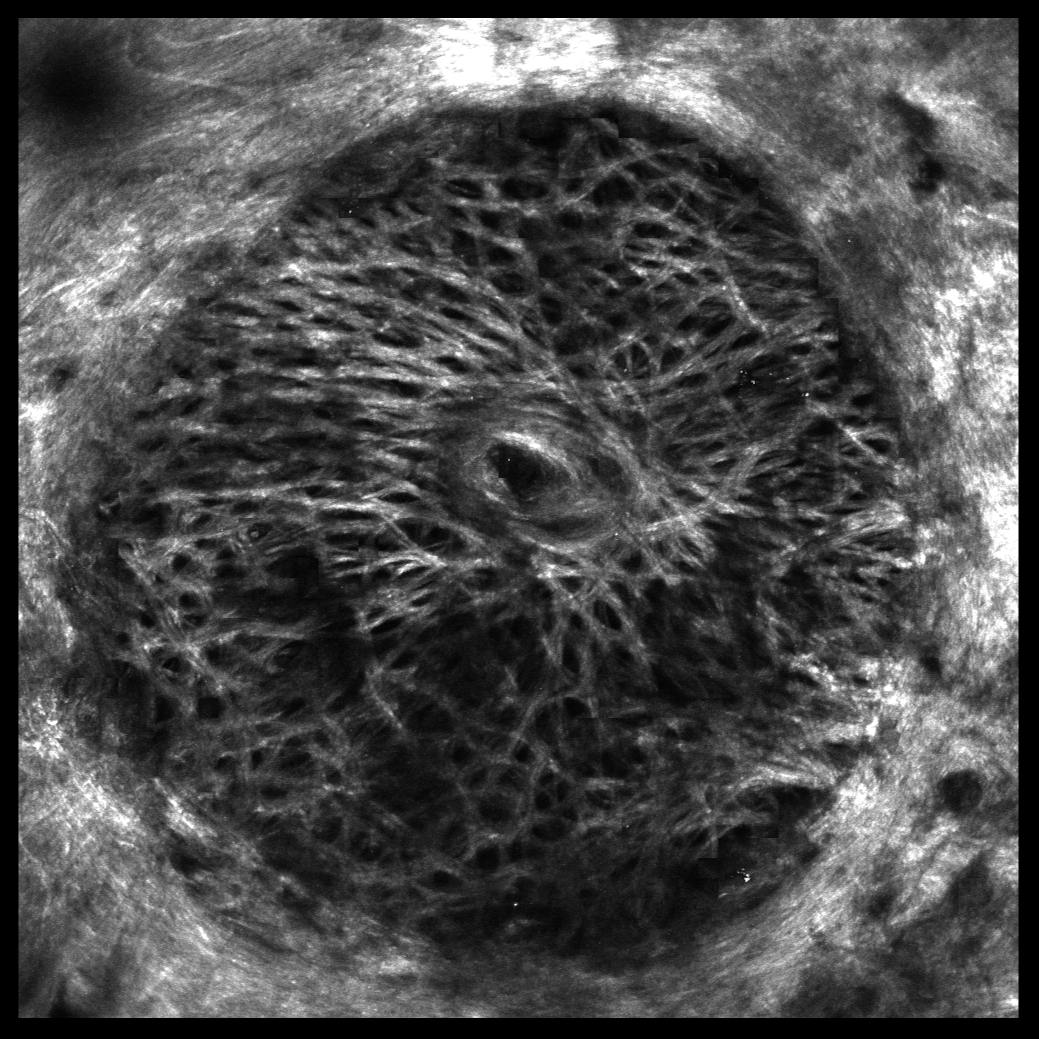

Segmentation and Registration of the Lamina Cribrosa Microstructure

alt text

Glaucoma is a group of neurodegenerative eye diseases characterized by gradual deterioration of retinal ganglion cells. Lamina cribrosa, a connective mesh-like trabecular tissue through which the retinal ganglion cells pass, is a potential location to identify the galucomatous condition of the eye. Therefore characterizing the biomechanics of the lamina cribrosa is essential for understanding the mechanisms leading to vision loss in glaucoma. In this project we have developed an automated system, where we use multiscale curvilinear structure enhancement and graph-cuts optimization to segment the mesh-like lamina cribrosa, and spectral graph theory-based approach to register the lamina cribrosa across different pressures.